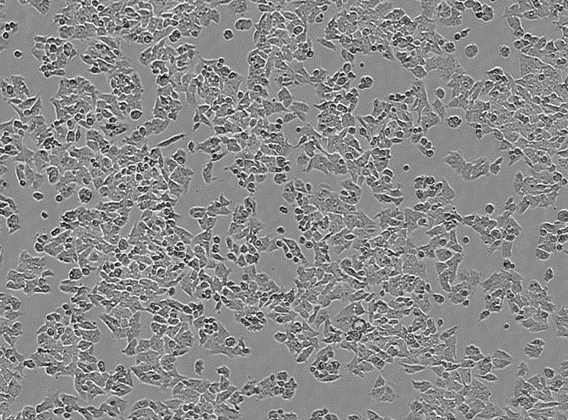

LoVo細(xì)胞的形態(tài)特征:

LoVo細(xì)胞呈現(xiàn)多邊形或不規(guī)則形態(tài),細(xì)胞邊界清晰,細(xì)胞核較大,染色質(zhì)豐富,核仁明顯。它們通常以貼壁生長(zhǎng)的方式在培養(yǎng)瓶底部形成單層細(xì)胞,并且在對(duì)數(shù)生長(zhǎng)期時(shí),細(xì)胞間接觸緊密。當(dāng)受到藥物刺激或環(huán)境應(yīng)激時(shí),LoVo細(xì)胞可能會(huì)表現(xiàn)出形態(tài)改變,如細(xì)胞皺縮、體積變小,甚至出現(xiàn)部分細(xì)胞脫落現(xiàn)象。

LoVo (Colorectal Cancer Cells)

Morphology Epithelial

Culture Properties Adherent

Celloger® Pro <10X Image>